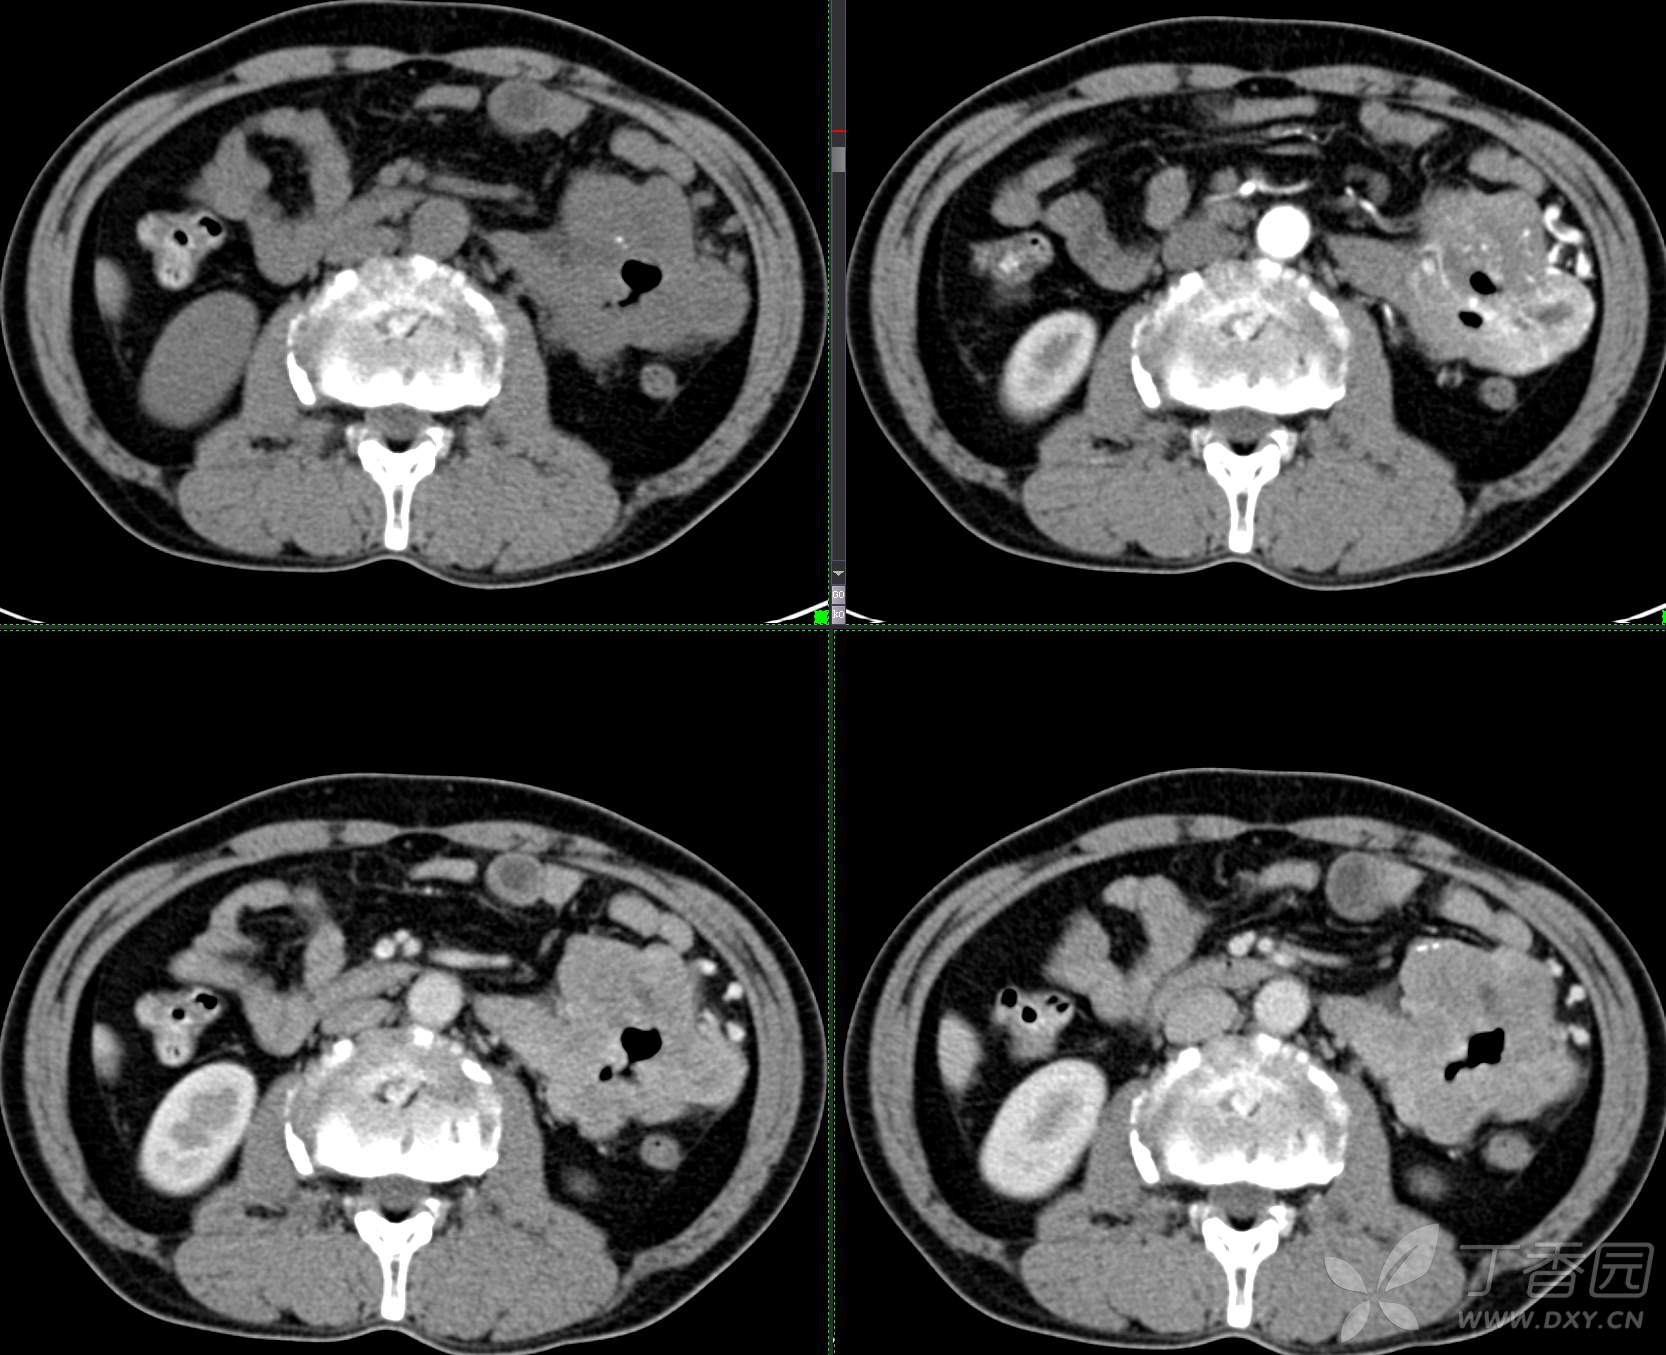

讨论:小肠病变,间质瘤?淋巴瘤?小肠腺癌?